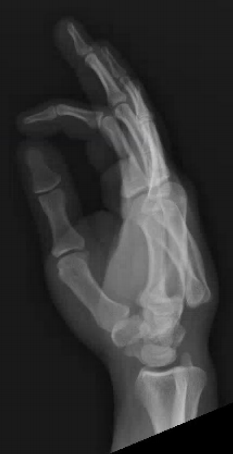

What’s the Diagnosis? Gepost op 4 maart 2019 door netwerkvsseh What’s the Diagnosis? By Dr. Loran Hatch @emdaily.cooperhealth.org Dit delen: Delen op X (Opent in een nieuw venster) X Share op Facebook (Opent in een nieuw venster) Facebook Delen op LinkedIn (Opent in een nieuw venster) LinkedIn E-mail een link naar een vriend (Opent in een nieuw venster) E-mail Afdrukken (Opent in een nieuw venster) Print Vind-ik-leuk Aan het laden... Gerelateerd